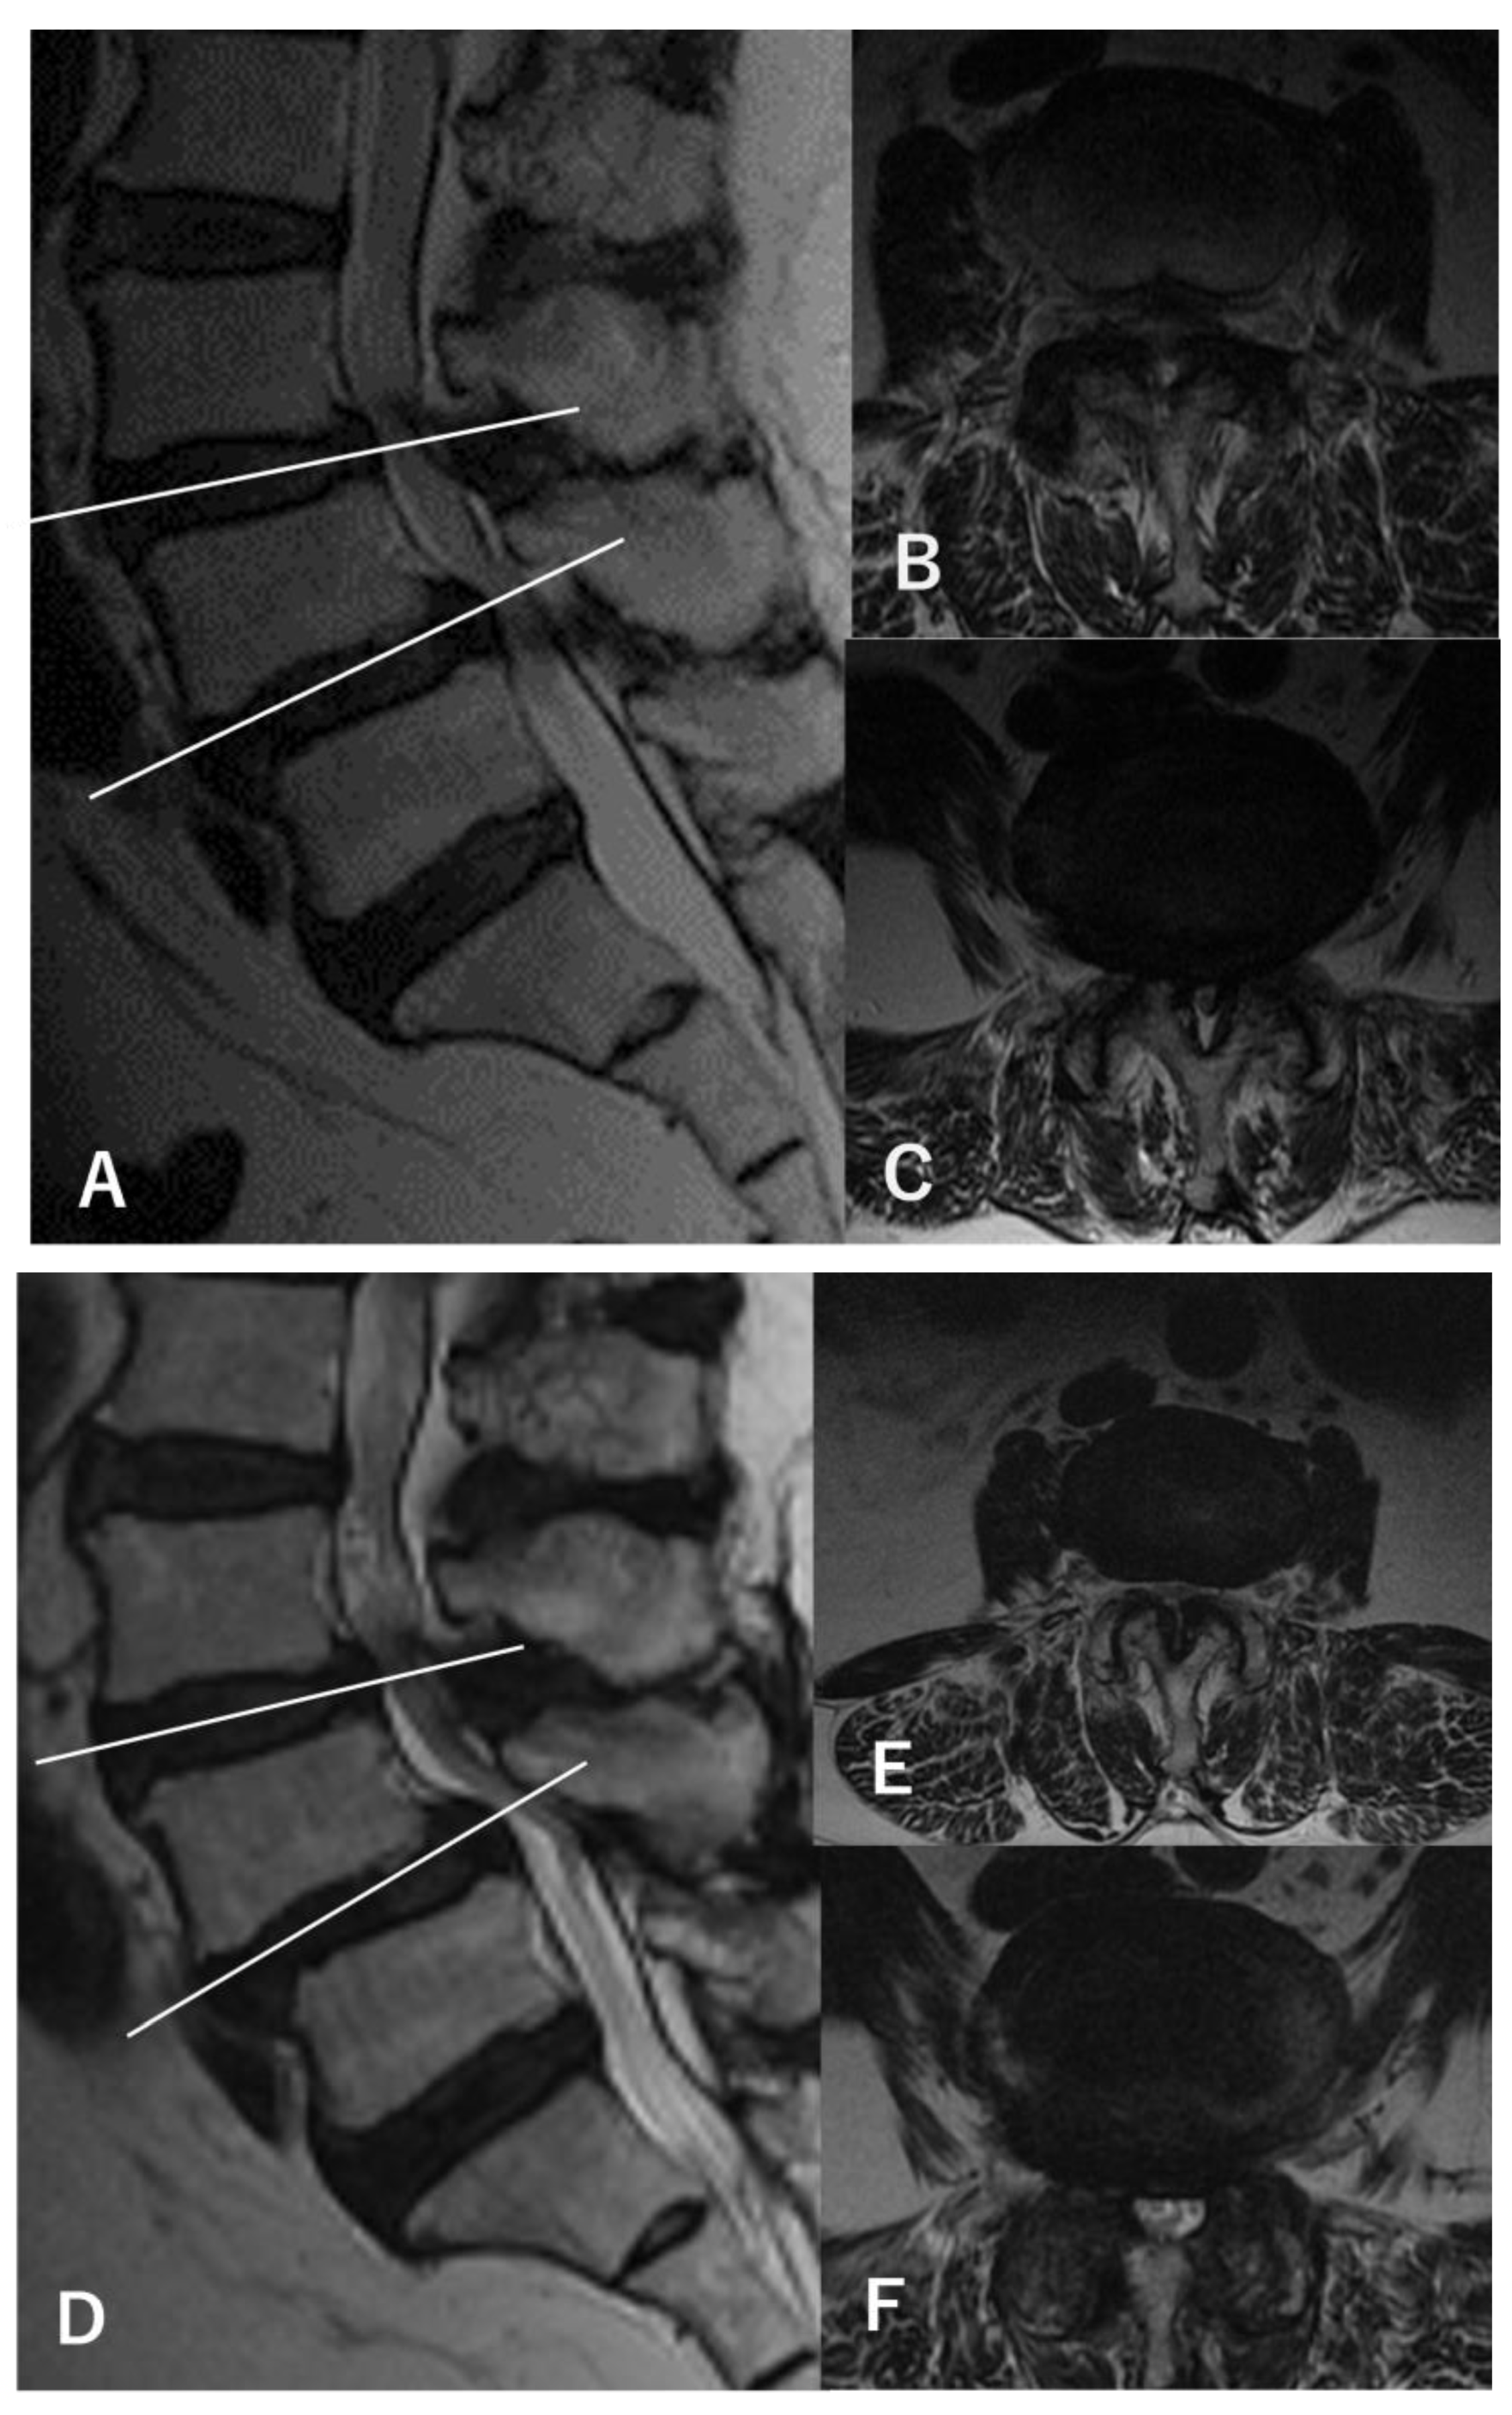

2.1. Definition of L3–4 Stenosis